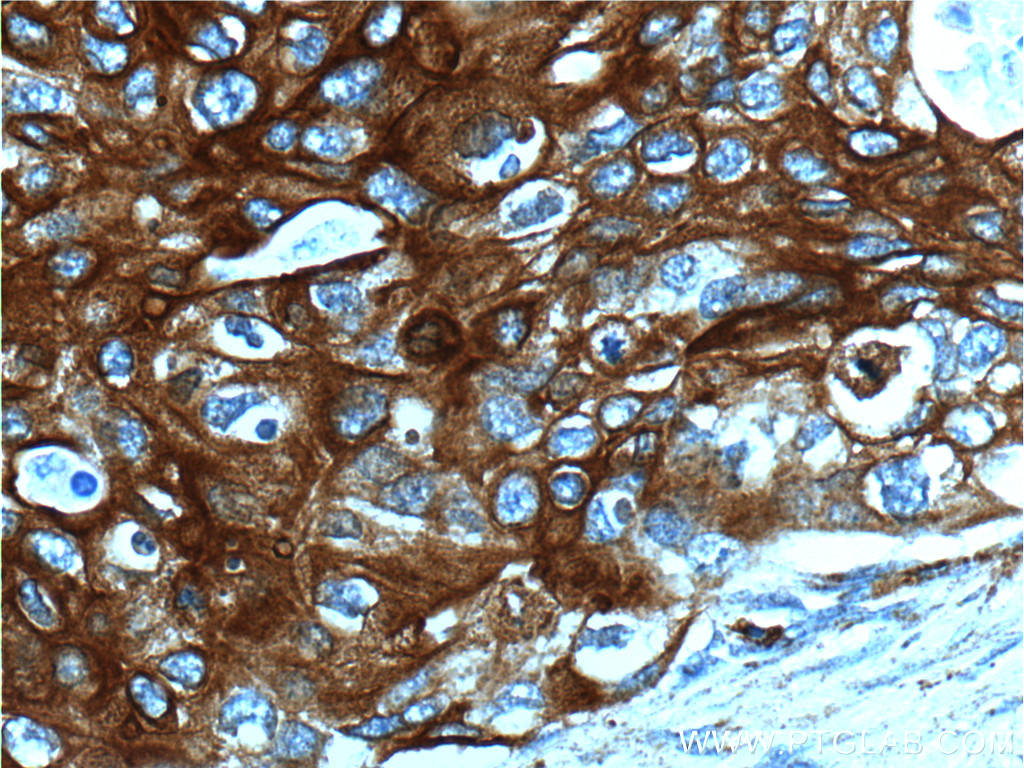

| Positive IHC detected in | human cervical cancer tissue, human oesophagus tissue Note: suggested antigen retrieval with TE buffer pH 9.0; (*) Alternatively, antigen retrieval may be performed with citrate buffer pH 6.0 |

| Immunohistochemistry (IHC) | IHC : 1:50-1:500 |

10164-2-AP targets Cytokeratin 13 in WB, IHC, IF/ICC, FC (Intra), IP, ELISA applications and shows reactivity with human, mouse samples.

Keratin 13 is a member of the keratin family. The keratins are intermediate filament proteins responsible for the structural integrity of epithelial cells and are subdivided into cytokeratins and hair keratins. Most of the type I cytokeratins consist of acidic proteins which are arranged in pairs of heterotypic keratin chains. This type I cytokeratin is paired with keratin 4 and expressed in the suprabasal layers of non-cornified stratified epithelia. Mutations in keratin 13 gene and keratin 4 have been associated with the autosomal dominant disorder White Sponge Nevus. The type I cytokeratins are clustered in a region of chromosome 17q21.2.